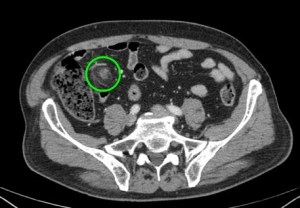

Se sospecha diverticulitis, se realiza TAC de abdomen:

Al igual que el caso anterior, nos encontramos nuevamente ante una apendagitis. Esta vez la sospecha era por diverticulitis, la anterior creíamos enfrentarnos a una apendicitis probablemente.

TAC: Imagen oval con aumento de la atenuación central, inferior a 5 cm de diámetro, contigüa al colon, con afectación de la grasa periférica. El aumento de la atenuación central es un signo de trombosis venosa muy útil para el diagnóstico, pero su ausencia no excluye en diagnóstico de apendagitis. Otros hallazgos, como aumento de la pared colónica o formación de abscesos son raros. Aunque los síntomas remiten en dos semanas, los cambios en la TAC pueden prolongarse más tiempo (pueden mantenerse, disminuir o quedar una atenuación residual), aunque en 6 mese suele haber remitido completamente. En Ecografía suele observarse en el área de máxima sensibilidad al dolor, una masa hiperecogénica, inferior a 5 cm, no compresible, adyacente al colon y sin señal Doppler.